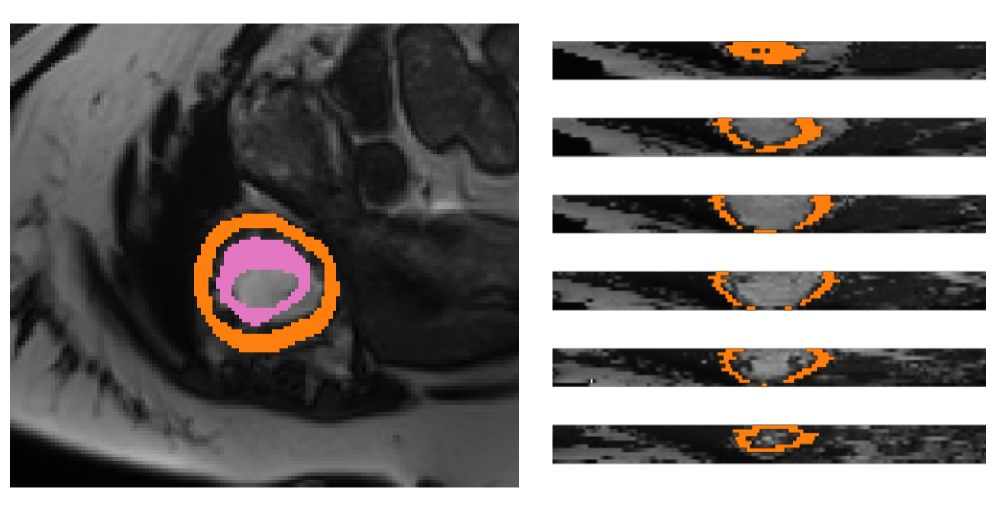

Because the cortical plate is the only class to identify, we expect to only use Module 2 of our method. However, as shown in Fig. 4, it forms a perforated sphere, opened at the level of the cerebellum (third and fourth slice of both rows). Consequently, the homology groups of the cortical plate are all trivial, and it cannot be detected with our method. In order to circumvent this issue, one could modify the image to force the appearance of homology—for instance by “closing” the sphere, as we did with the myocardium in 3D. Instead, we suggest a different strategy: we study the image slice by slice, in the coronal plane.

We observed that most slices fall into one of three types: the cortical plate forms either (i) one circle (first two slices in both rows of Fig. 4), (ii) two disjoint circles (last slice), or (iii) an “open circle”, i.e., a circular arc (third and fourth slices). These cases are identified by inspecting the persistence diagram as follows.

-

•

We consider the sublevel set filtration of the slice and compute its -persistence. For each point, we compute the associated connected component, as described in Module 2 (component of the birth pixel at birth time).

Next, we discard points in the diagram that correspond to implausible segmentations. This is done by identifying the corresponding connected component, and checking whether the hole it encloses has a number of pixels within . In practice, we found that the values 25% and 75% of the slice area are suitable.

Last, we select the “optimal feature” from the remaining points, as described in the next paragraph. We classify a slice as type (ii) if there exists another point of the diagram at distance at most , a fixed threshold, and type (i) otherwise. For simplicity, slices of type (iii) are treated as type (i).

The final segmentation is defined as the union of the connected components associated with the selected points—one point for types (i) and (iii), and two points for type (ii).